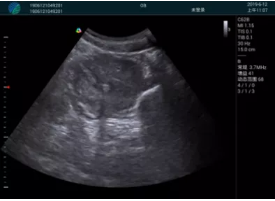

頸動(dòng)脈血流充盈飽滿,無外溢